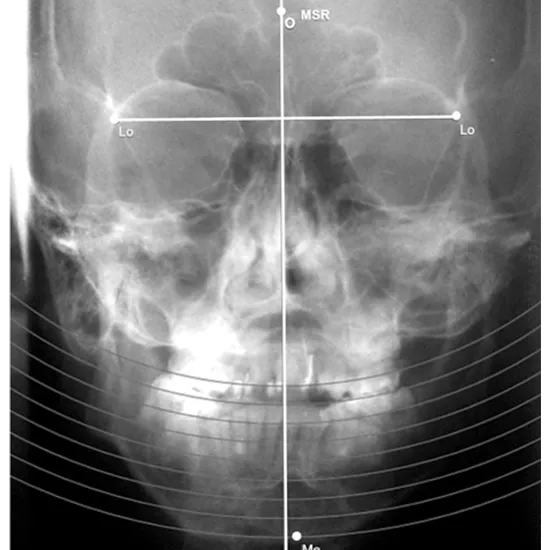

What is an X-ray Mandible Pa Left Lateral Oblique Test?

An X-ray of the mandible, also known as the jaw, can be used to examine the structures of the jaw bone, the TM joint (temporomandibular joint), and the surrounding soft tissues, such as the muscles.